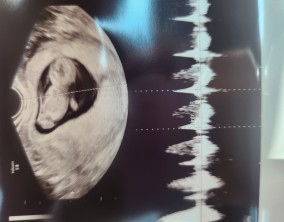

눈물로 실감한 아홉 번째 주